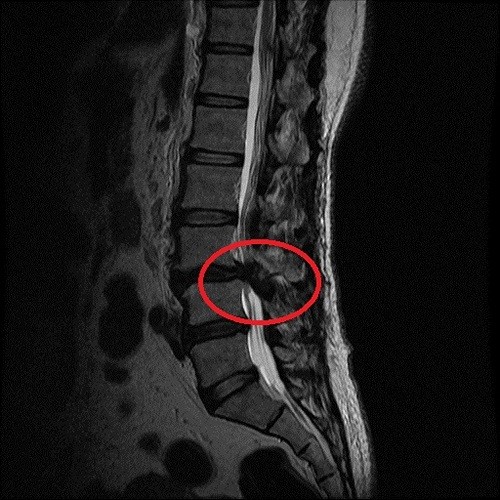

左圖:從影像學檢查發現,高女士的神經壓迫情況很嚴重,細細的神經柱就像被掐住一樣。

從影像學檢查發現,高女士的神經壓迫情況很嚴重,細細的神經柱就像被掐住一樣,加上高女士的腎功能差,幾乎只剩下健康人的十分之一左右時,更增加了手術的困難度。吳聖文醫師表示,脊椎微創手術的優點就是傷口小失血量少,不必破壞大量的肌肉和骨頭,在特殊工具和高倍率顯微鏡的幫助下,一樣可以做到神經完全減壓的效果,並儘量保有脊椎本身的骨性結構,最後再透過幾個一公分的小傷口將骨釘置入和固定,達成最後的融合過程。